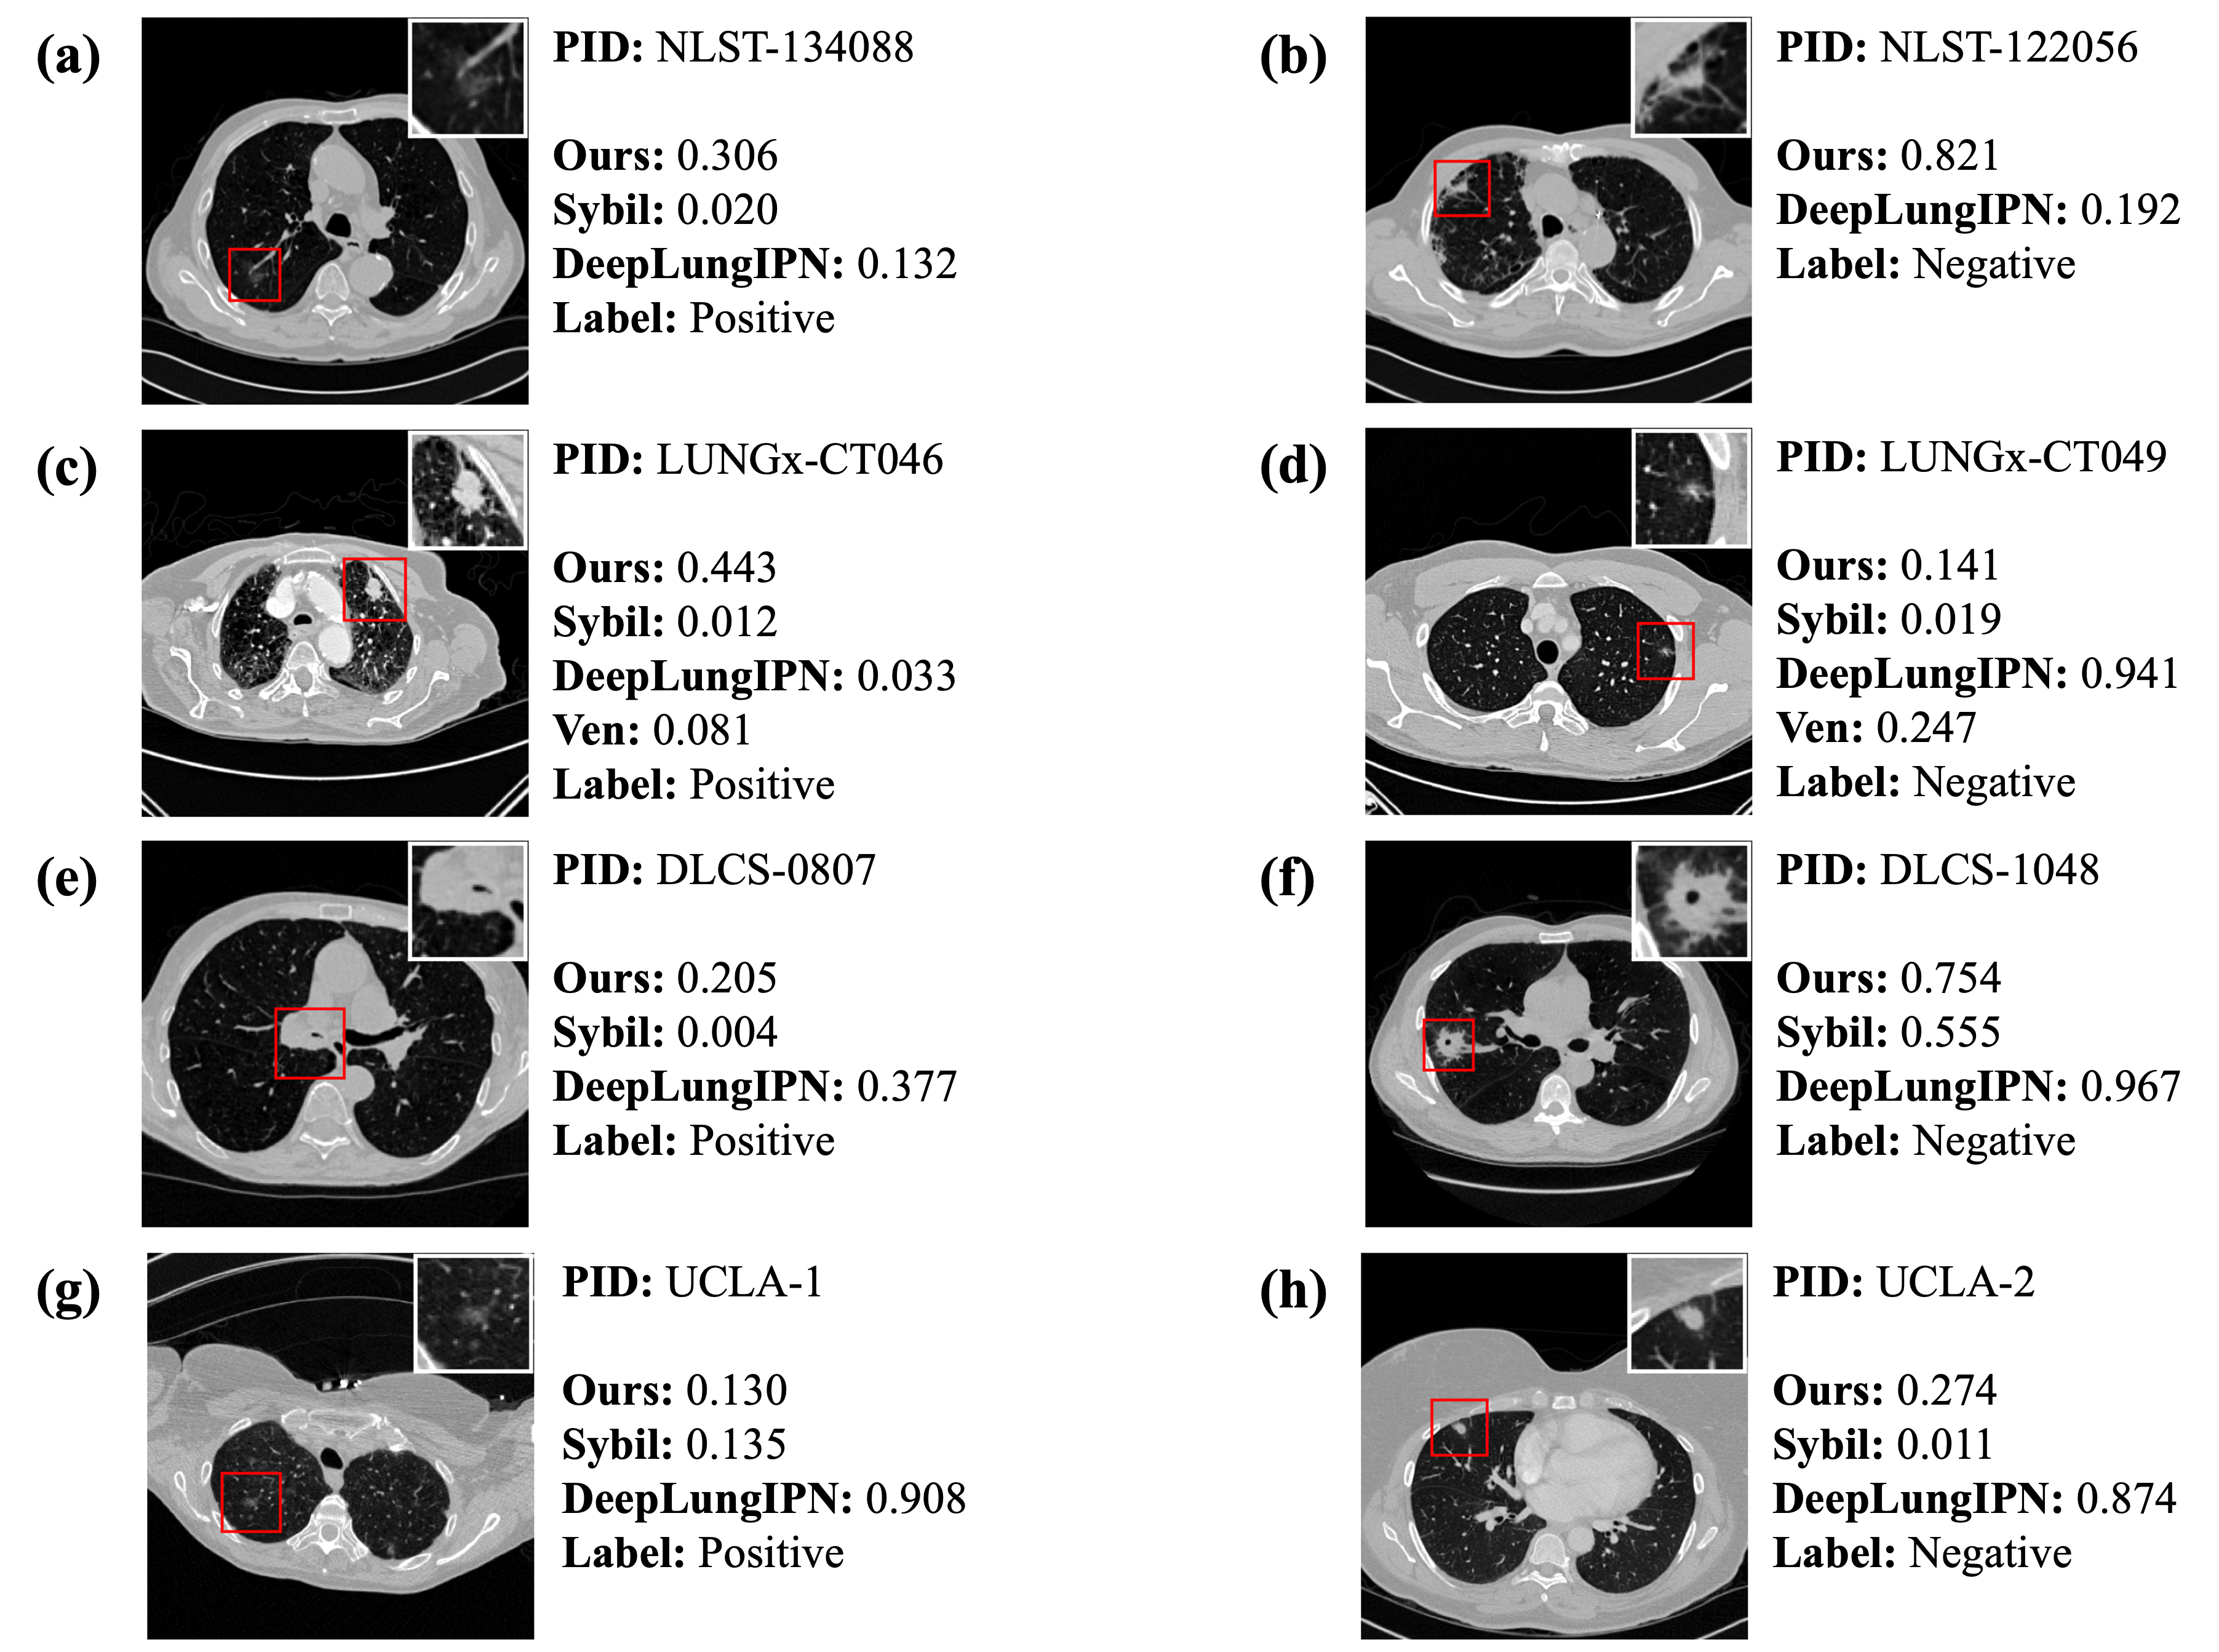

4.4 Error Analysis

In Fig. 3, we present a CT scan from a lung cancer patient and a non-lung cancer patient for each dataset. More examples are shown in Fig. A1. It is important to note that both Sybil and DeepLungIPN use only the CT scan as input, whereas our model and that of Venkadesh et al. incorporate both the CT scan and the nodule location as inputs. Although the pipeline in DeepLungIPN involves a nodule detection step, the detected nodules may not correspond to the annotated nodules shown in the figure.

In Fig. 3a and c, all models fail to identify the patient as high-risk even though they are diagnosed with lung cancer within a year. In Fig. 3a, the nodule crop shows a poorly marginated, pure ground glass nodule with an irregular margin. The malignant nodule in Fig. 3c is spiculated with a complex shape, septal stretching, and vascular convergence. Our model outputs relatively higher risk scores of 0.306 and 0.443, in contrast to the extremely low scores given by other models. Fig. 3e illustrates a challenging and uncommon case where the nodule is within the right main stem bronchus. All models assign a relatively lower score while the nodule is malignant. In Fig. 3g, a poorly marginated pure ground glass nodule is presented. Among the models, only DeepLungIPN successfully assigns a high risk score to this malignant case, while the others fail.

Fig. 3b shows a non-cancerous case with a lobulated and serrated nodule exhibiting complex shape and pleural retraction. While DeepLungIPN correctly identifies the case as low risk, our model assigns a high risk score of 0.821. In contrast, Fig. 3d and h illustrate two negative cases where DeepLungIPN assigns unusually high risk scores, whereas our model and others provide more conservative estimates. This discrepancy may stem from DeepLungIPN’s miscalibration, leading to overconfident predictions. Additionally, visual inspection revealed that DeepLungIPN sometimes detects non-nodule regions, which may contribute to inflated risk scores. In Fig. 3f, although the biopsy confirmed a benign finding, the nodule appears highly suspicious due to its large size, irregular shape, and spiculated margins. All models, including ours, assign high risk scores to this case. Radiologists also classified it as Lung Imaging Reporting and Data System (Lung-RADS) category 4X, indicating a high suspicion of malignancy with additional concerning imaging features [40].

Fig. A1c, e, and g depict nodules diagnosed as lung cancer, but our model underestimates the risk. Although these nodules are relatively small, they exhibit irregular shapes (c), spiculated margins (e), mixed densities (g), and pleural attachment (c, e, g). Interestingly, all other models also predict low scores for these nodules. In Fig. A1a, a lobulated, solid, well-marginated nodule is shown with a few suspicious features. It is reasonable that our model predicts a 33% likelihood of malignancy, but all other models assign extremely low scores to this cancer patient.

In Fig. A1b, the nodule is solid with spiculated and lobulated margins and an irregular shape. Concerning characteristics include cyst-like spaces and pleural retraction. In Fig. A1d, the nodule appears to be solid with spiculated margins, septal stretching, and vascular convergence. In Fig. A1h, a large, part-solid nodule with poorly defined margins is observed. Given these suspicious features, most models assign relatively higher risk scores, despite the patient not being diagnosed with lung cancer. However, in Fig. A1h, Sybil accurately identifies it as having a lower score. In contrast, Fig. A1f shows a tiny nodule with no apparent suspicious features, but DeepLungIPN assigns a comparatively higher risk. We found that the nodules detected by DeepLungIPN appear to be fibrosis and vessels.